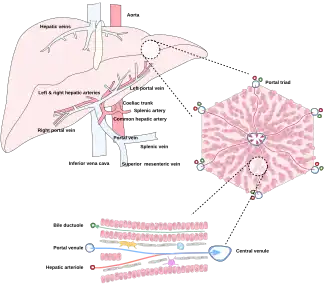

The liver is connected to two large blood vessels: the hepatic artery and the portal vein. The hepatic artery carries oxygen-rich blood from the aorta via the celiac trunk, whereas the portal vein carries blood rich in digested nutrients from the entire gastrointestinal tract and also from the spleen and pancreas.[11] These blood vessels subdivide into small capillaries known as liver sinusoids, which then lead to hepatic lobules.

Microscopically, each liver lobe is seen to be made up of hepatic lobules. The lobules are roughly hexagonal, and consist of plates of hepatocytes, and sinusoids radiating from a central vein towards an imaginary perimeter of interlobular portal triads.[24] The central vein joins to the hepatic vein to carry blood out from the liver. A distinctive component of a lobule is the portal triad, which can be found running along each of the lobule's corners. The portal triad consists of the hepatic artery, the portal vein, and the common bile duct.[25] The triad may be seen on a liver ultrasound, as a Mickey Mouse sign with the portal vein as the head, and the hepatic artery, and the common bile duct as the ears.[26]

Blood supply

The liver gets its blood supply from the hepatic portal vein and hepatic arteries. The hepatic portal vein delivers around 75% of the liver's blood supply and carries venous blood drained from the spleen, gastrointestinal tract, and its associated organs. The hepatic arteries supply arterial blood to the liver, accounting for the remaining quarter of its blood flow. Oxygen is provided from both sources; about half of the liver's oxygen demand is met by the hepatic portal vein, and half is met by the hepatic arteries.[46] The hepatic artery also has both alpha- and beta-adrenergic receptors; therefore, flow through the artery is controlled, in part, by the splanchnic nerves of the autonomic nervous system.

Blood flows through the liver sinusoids and empties into the central vein of each lobule. The central veins coalesce into hepatic veins, which leave the liver and drain into the inferior vena cava.[47]

The liver and its veins -

Diagram of liver, lobule, and portal tract and their inter-relations